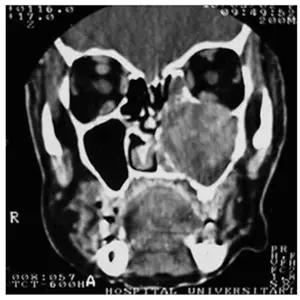

sinus x ray

If you have symptoms of a sinus mucocele, it is always essential to consult a Rhinologist for an accurate diagnosis and treatment plan. The history of prior sinus surgery or facial trauma is also helpful in establishing the diagnosis. A CT scan (x- ray) of your sinuses and nasal endoscopy (looking inside the nose with a small camera) is essential to better assess the problem.